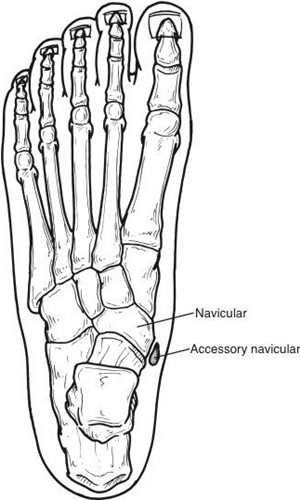

주상골(navicular bone)은 발목뼈(족근골)(tarsal bone)를 구성하는 뼈(bone) 중 하나입니다. 위치상으로 살펴봤을 때 입방골(cuboid bone)과 설상골(cuneiform bone), 그리고 거골(talus) 사이에 자리 잡은 뼈(bone)입니다. 그렇다 보니 방향적인 위치상 발목 안쪽(internal ankle)으로부터 타고 내려와, 실질적으로 발의 아치(foot arch)가 가장 높게 실리게 되는 위치상에 존재하게 됩니다. 주상골(navicular bone)의 자세한 모습과 위치는 사진을 통해서 제대로 살펴볼 수 있습니다.

사진에서 살펴본 것과 같이 주상골(navicular bone)은 단일한 뼈(bone)입니다. 하지만 부주상골증후군(accessory navicular syndrome)은 주상골(navicular bone)이 하나가 아닌 증상과도 같습니다. 그래서 그 이외의 뼈(bone)를 부주상골(accessory navicular bone)이라 부릅니다. 기본적으로 부주상골(accessory navicular bone)은 더 작은 크기(small size)로 형성되어있으며, 그 위치는 부주상골(accessory navicular bone)이라는 이름답게 주상골(navicular bone) 옆(lateral)에 자리 잡게 됩니다.